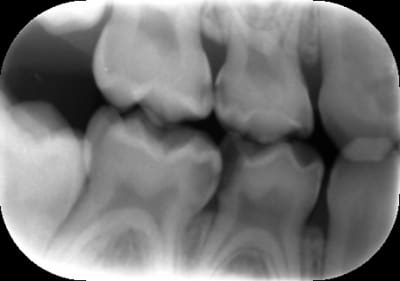

- Il y a effectivement une lésion proximale qu'il aurait été bien de détecter. En pédo encore plus que chez l'adulte, un bilan radio pré-op est indispensable. Je fais systématiquement deux clichés BW : et si j'ai le moindre doute sur l'état d'une furcation ou d'une lésion proximale, je complète par des rétro-alvéolaire. (exemple ci-dessous)